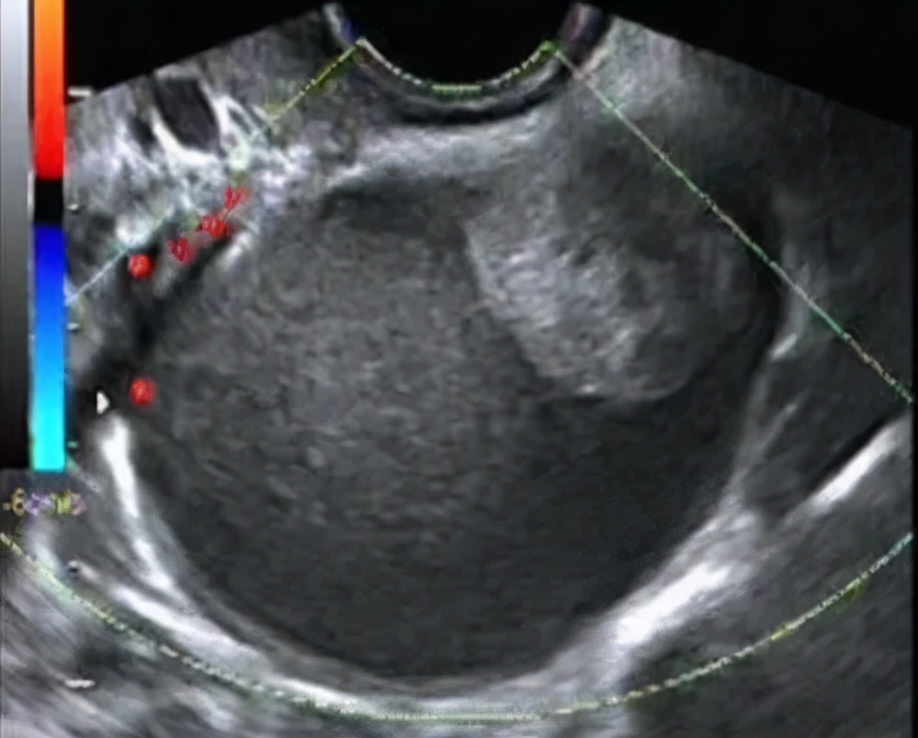

卵巢子宫内膜异位囊肿特点: 囊肿可在双侧卵巢或单侧卵巢发病,因病程的长短及月经周期时相不同,表现不同,可伴有痛经、也有不痛经,体检的时候才被发现的,早期超声表现与黄体血肿类似,典型的成熟巧囊表现为囊肿内细密均匀的光点状回声。需要动态复查,酌情手术治疗及辅助治疗;个别巧囊经过长时间的演进,也有变成癌的,所以也要引起重视!